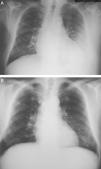

Observación clínicaVarón de 79 años, sin hábitos tóxicos ni alergias, diagnosticado de enfermedad de Parkinson en tratamiento oral con levodopa (250mg/día), hidrocloruro de metilfenidato (20mg/día), rasagilina (1mg/día) y, en los últimos 12 meses, cabergolina (2mg/día). Treinta días antes de su ingreso presentó un cuadro catarral persistente con tos, expectoración mucosa y aumento progresivo de la disnea, sin dolor torácico, síndrome constitucional ni fiebre. Tras seguir tratamiento con levofloxacino oral no experimentó mejoría, de modo que se le realizó una radiografía que evidenció un derrame pleural izquierdo sin pérdida de volumen ni condensaciones (fig. 1A). La exploración física descartó signos de insuficiencia cardíaca, trombosis venosa o adenopatías palpables. En la auscultación cardíaca se detectó un soplo sistólico sin tercer ruido ni alteraciones del ritmo, y en la respiratoria se observó una semiología de derrame pleural izquierdo sin estertores ni signos de broncoespasmo.

Ante estos hallazgos se procedió a retirar únicamente la cabergolina, se inició fisioterapia respiratoria y se instauró tratamiento diurético para obtener un equilibrio hídrico negativo. A los 2 meses, una radiografía de control confirmó la clara disminución del derrame pleural y se retiraron los diuréticos. A los 10 meses el paciente se encontraba asintomático y no se observó derrame pleural en la radiografía (fig. 1B). En el ecocardiograma de control ya no se apreciaba la dilatación de las cavidades derechas, la insuficiencia tricuspídea era mínima, la presión pulmonar era de 32 mmHg y la insuficiencia mitral, ligera.